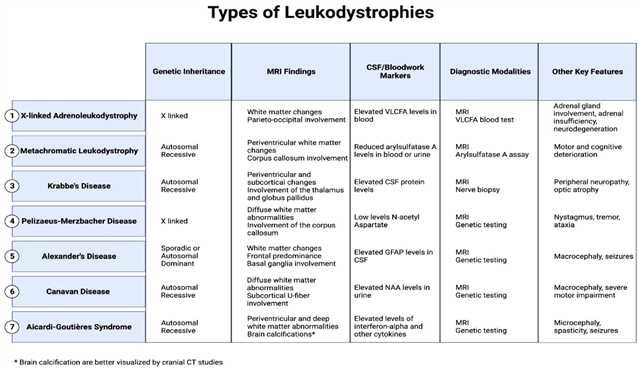

该综述重点解析了X - 连锁肾上腺脑白质营养不良、异染性脑白质营养不良、克拉伯病、佩梅病、亚历山大病、卡纳万病、Aicardi-Goutières 综合征7 种经典类型,明确了各自的 “影像学指纹” 与诊断标志物。

脑白质营养不良中的主要磁共振成像表现、脑脊液 / 血液标志物及其他关键特征

一、7 种脑白质营养不良核心诊断要点

1. X - 连锁肾上腺脑白质营养不良(最常见)

由 X 染色体 ABCD1 基因突变导致极长链脂肪酸异常蓄积,主要累及男性。

• MRI 特征:胼胝体与顶枕部白质出现融合性高信号病灶,伴随钆增强强化,疾病后期可累及全脑白质;脊髓 MRI 可见皮质脊髓束与后柱变性。

• 辅助检查:血液极长链脂肪酸水平升高,新生儿筛查可早期发现。

2. 异染性脑白质营养不良

常染色体隐性遗传,芳基硫酸酯酶 A 缺乏导致硫苷脂蓄积。

• MRI 特征:早期脑室周围白质对称性脱髓鞘,进展后出现特征性 **“虎纹征” 与 “豹纹征”**,胼胝体压部受累为典型标志。

• 辅助检查:芳基硫酸酯酶 A 活性显著降低,尿硫苷脂升高。

3. 克拉伯病(球形细胞脑白质营养不良)

GALC 基因突变致病,婴幼儿期发病凶险。

• MRI 特征:丘脑、皮质下白质异常信号,婴儿型可见视神经与颈髓膨大。

• 辅助检查:脑脊液鞘氨醇蓄积,新生儿筛查是干细胞移植获益的关键。

4. 佩梅病

X 连锁隐性遗传,PLP1 基因突变导致髓鞘生成障碍。

• MRI 特征:内囊、放射冠、视辐射区髓鞘缺失,T1 低信号、T2 弥漫高信号。

• 典型症状:眼球震颤、痉挛性瘫痪、共济失调。

5. 亚历山大病

GFAP 基因突变导致罗森塔尔纤维形成,额叶白质受累为主。

• MRI 诊断标准:满足广泛额叶白质异常、脑室周围边缘信号改变、基底节与丘脑受累、脑干异常、病灶强化 5 项中 4 项即可确诊。

• 辅助检查:脑脊液 GFAP 水平升高。

6. 卡纳万病

常染色体隐性遗传,ASPA 基因突变致 N - 乙酰天冬氨酸蓄积。

• MRI 特征:皮质下 U 纤维弥漫性 T2 高信号,伴巨头畸形。

• 鉴别要点:磁共振波谱 NAA 显著升高,可与亚历山大病区分。

7. Aicardi-Goutières 综合征

神经炎症性疾病,酷似先天性宫内感染。

• MRI 特征:脑室周围白质丢失、基底节与齿状核钙化,胼胝体变薄、脑室扩大。

• 辅助检查:脑脊液干扰素 -α、新蝶呤升高。